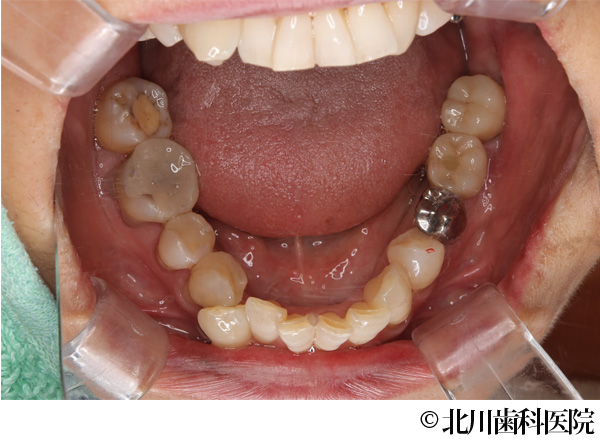

【症例1】インプラントと自家歯牙移植にて機能回復を行った症例

- 治療後

- インプラントと自家歯牙移植にて機能回復を行った症例

- 737,000円(税込)

- 1年3ヵ月

- 女性・50代

左下の奥歯が腫れて痛みがあり、抜歯後にインプラントを希望されて来院されました。

左下の奥歯は2本分の歯を喪失することになるため、抜歯する予定の歯の一つ手前にインプラントを埋め込み、抜歯部には親知らずを移植しクラウン(被せ物)を装着することで対応しました。

インプラントと移植歯により喪失した歯を補うことができ、審美面・機能面の回復につながりました。また、インプラント埋入と同時に移植を行うことで手術が一度に終わり身体の負担を軽減して行うことができました。